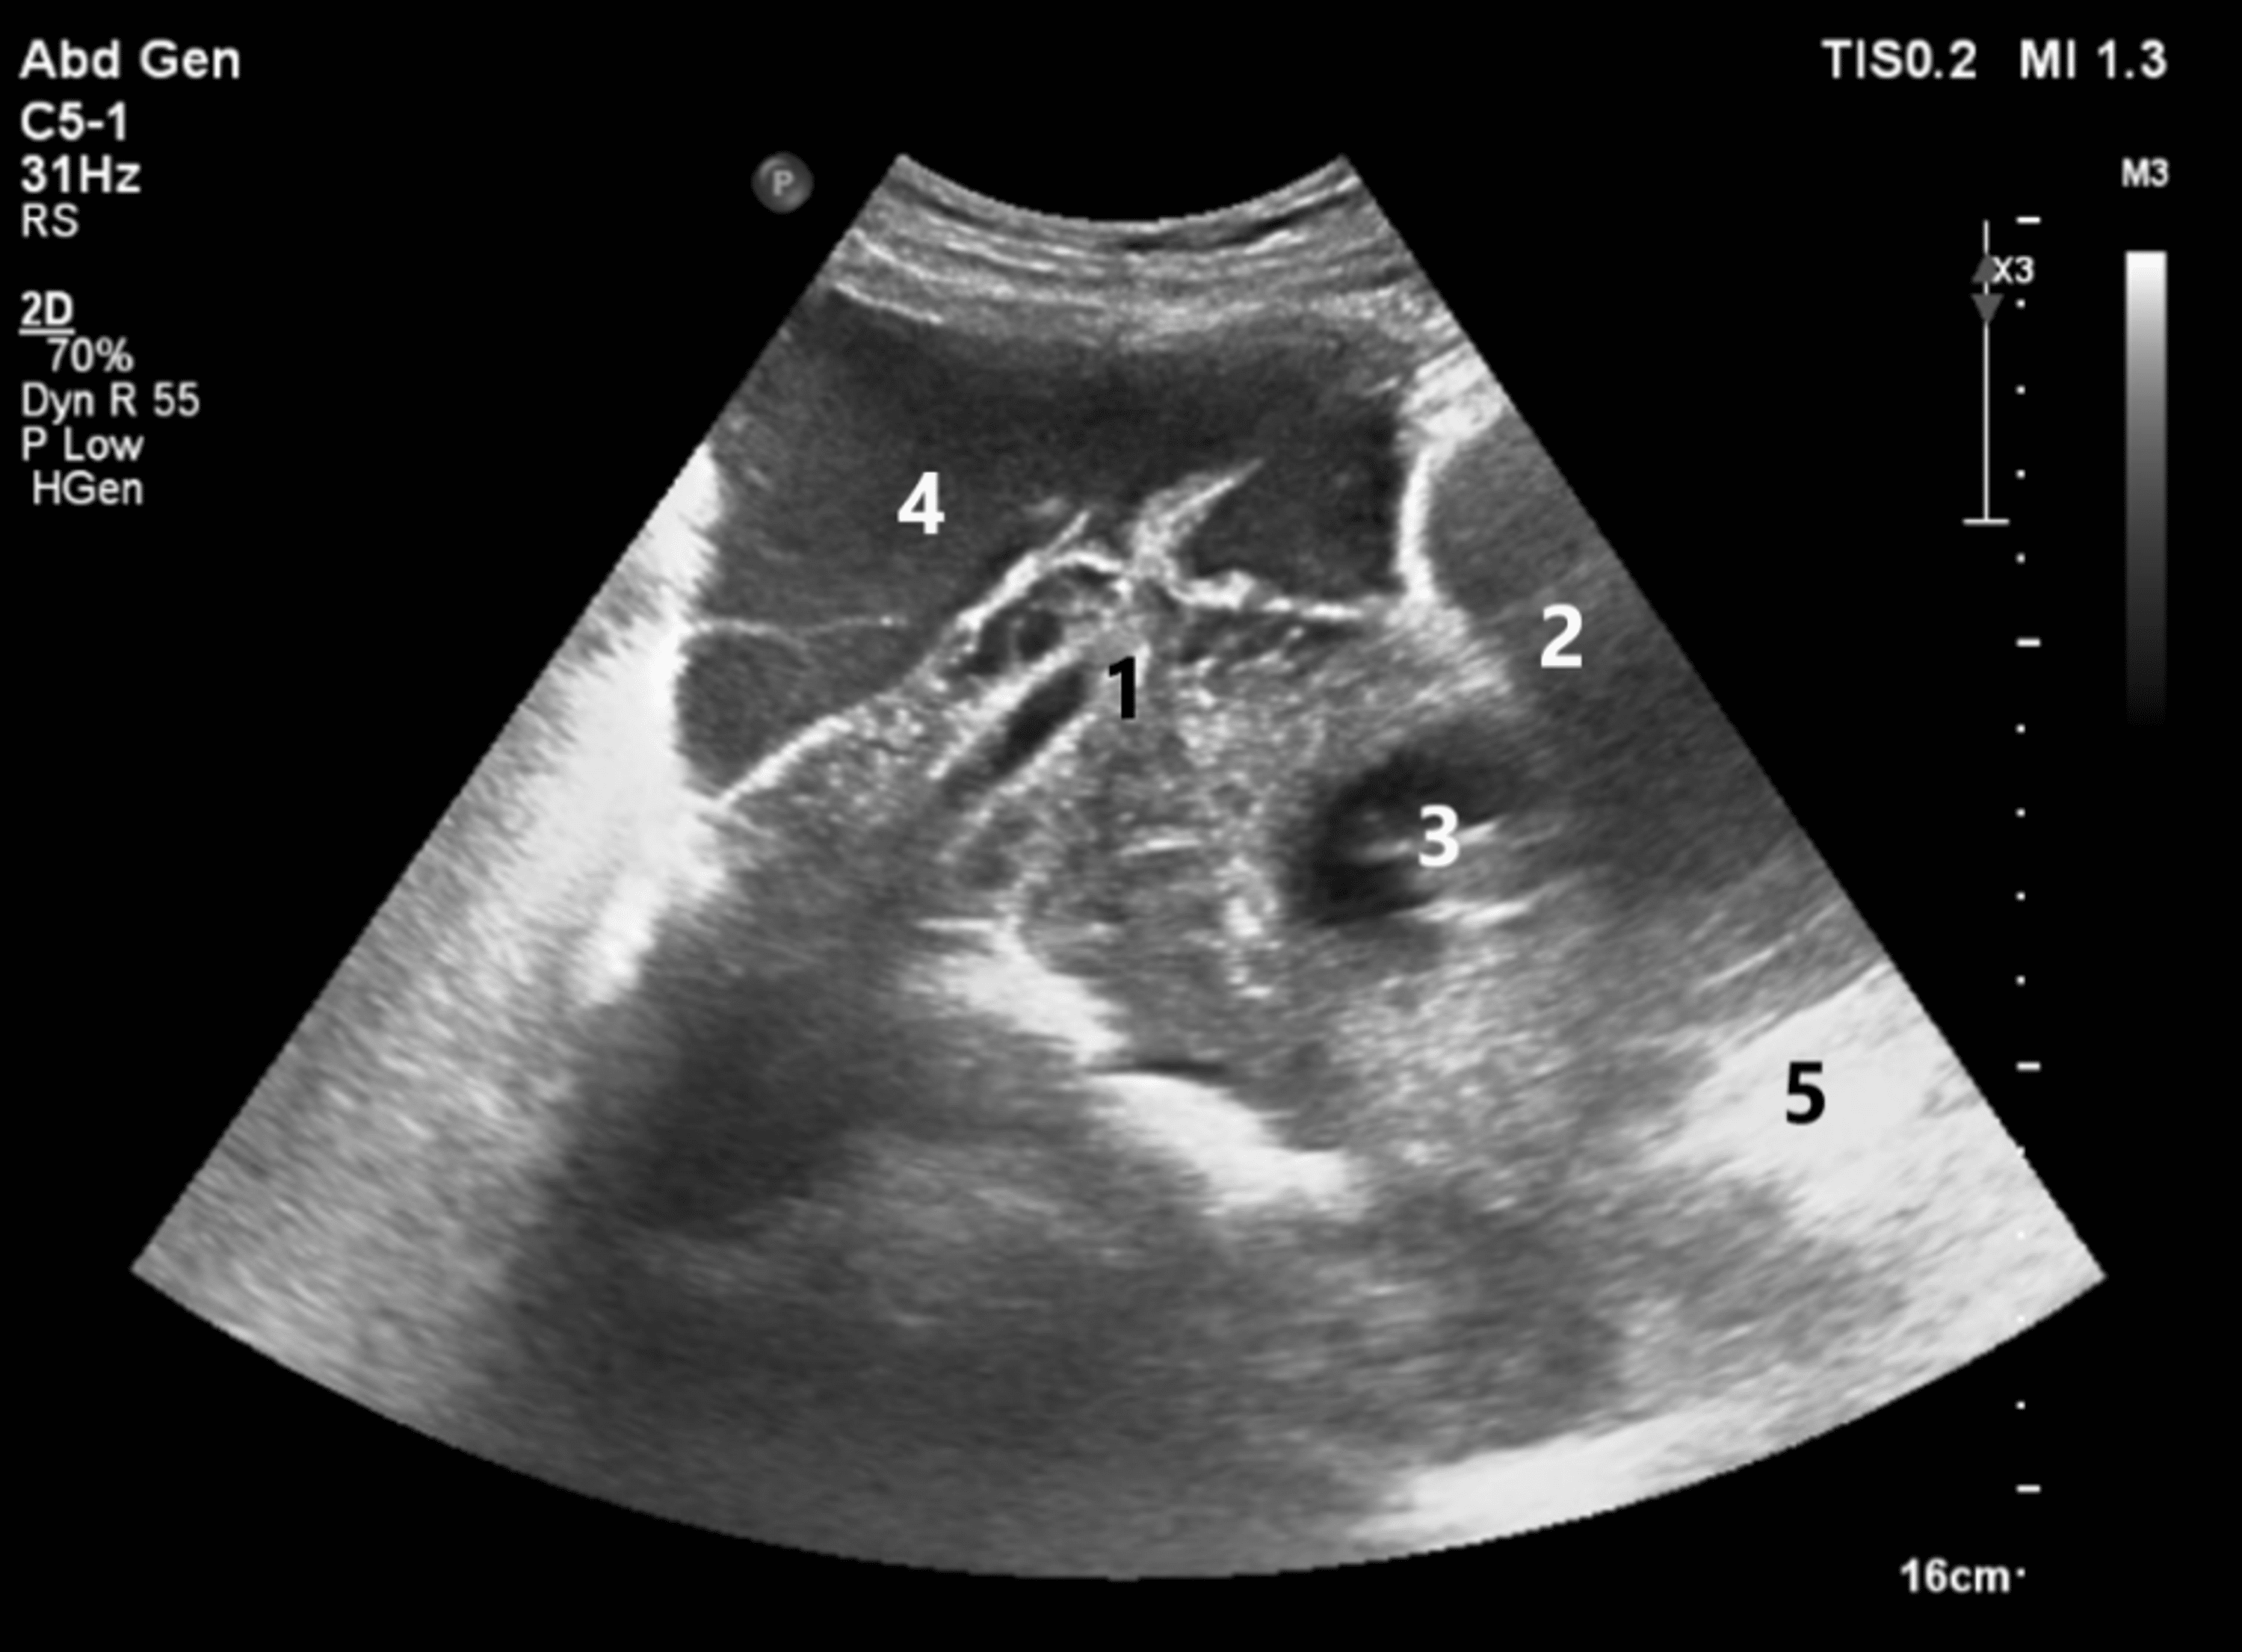

Ultrasound Leadership Academy Ultrasound in Early Pregnancy — EM Curious

From www.emcurious.com

Ultrasound Leadership Academy Ultrasound in Early Pregnancy — EM Curious What Does Debris In Uterus Mean Fluid in the endometrial cavity is the accumulation of liquid within the uterus lining. Endometrial hyperplasia is a condition in which the lining of your womb becomes too thick due to hormonal imbalance. Fluid in the endometrial canal can be caused by various factors, such as menstrual cycle, infections, polyps, fibroids, adenomyosis,. It can be caused by menstrual cycle changes,.. What Does Debris In Uterus Mean.